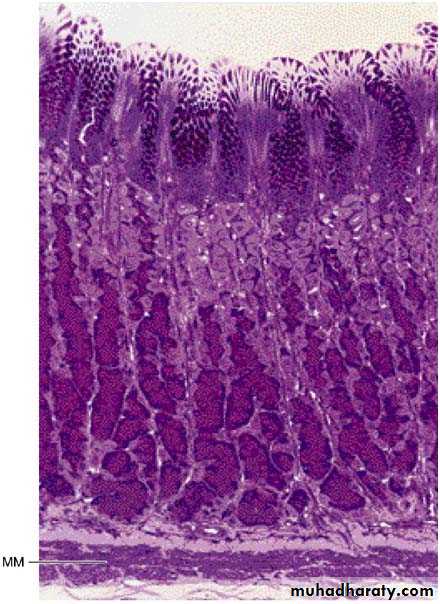

Photomicrograph of a section of the gastric glands in the fundus of the stomach. Note the superficial mucus-secreting epithelium. Parietal cells (light-stained) predominate in the mid and upper regions of the glands; chief (zymogenic) cells (dark-stained) predominate in the lower region of the gland. MM, muscularis mucosae. PT stain. Low magnification.